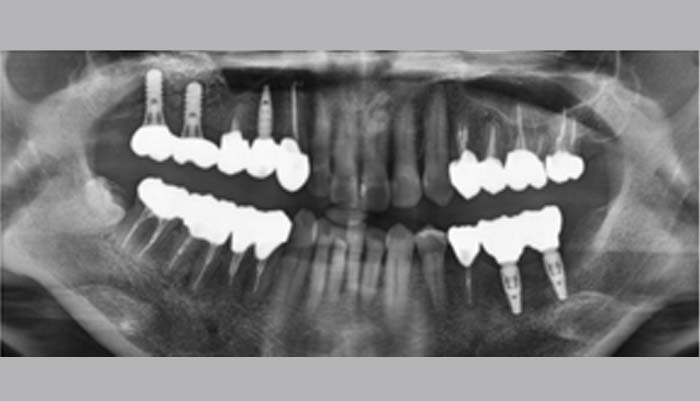

症例紹介